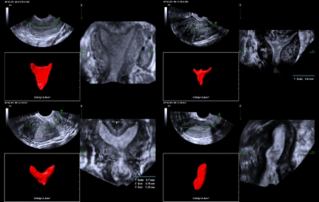

![ultrasonic-diagnosis-mullerian-duct-anomalies.thumb.319.319 Ultrasound Journal 39 - Ultrasonic Diagnosis of M├╝llerian Duct Anomalies]() Ultrasound Journal 39 - Ultrasonic Diagnosis of M├╝llerian Duct AnomaliesHow 3D transvaginal ultrasound replaced MRI for detecting uterine malformations. Septate uterus case demonstrates Smart ERA's role in reproductive imaging. Evidence-based diagnosis.Ultrasound Cases | Ultrasound | Smart applications | OB GYN 2025-12-04

Ultrasound Journal 39 - Ultrasonic Diagnosis of M├╝llerian Duct AnomaliesHow 3D transvaginal ultrasound replaced MRI for detecting uterine malformations. Septate uterus case demonstrates Smart ERA's role in reproductive imaging. Evidence-based diagnosis.Ultrasound Cases | Ultrasound | Smart applications | OB GYN 2025-12-04 -

![smart-era-diagnosis-mullerian-duct-abnormalities.thumb.319.319 Ultrasound Journal 33 - Use of Smart ERA in diagnosis of Ultrasound Journal 33 - Use of Smart ERA in diagnosis of M├╝llerian duct abnormalities duct anomalies]() Ultrasound Journal 33 - Use of Smart ERA in diagnosis of Ultrasound Journal 33 - Use of Smart ERA in diagnosis of M├╝llerian duct abnormalities duct anomaliesDiscover how Mindray's Smart ERA technology revolutionizes the diagnosis of M├╝llerian duct abnormalities using AI-based 3D ultrasound, providing accurate and automated endometrial cavity imaging for improved gynecological care.Ultrasound Cases | Intelli-Digital | Ultrasound | OB GYN 2025-01-14

Ultrasound Journal 33 - Use of Smart ERA in diagnosis of Ultrasound Journal 33 - Use of Smart ERA in diagnosis of M├╝llerian duct abnormalities duct anomaliesDiscover how Mindray's Smart ERA technology revolutionizes the diagnosis of M├╝llerian duct abnormalities using AI-based 3D ultrasound, providing accurate and automated endometrial cavity imaging for improved gynecological care.Ultrasound Cases | Intelli-Digital | Ultrasound | OB GYN 2025-01-14 -